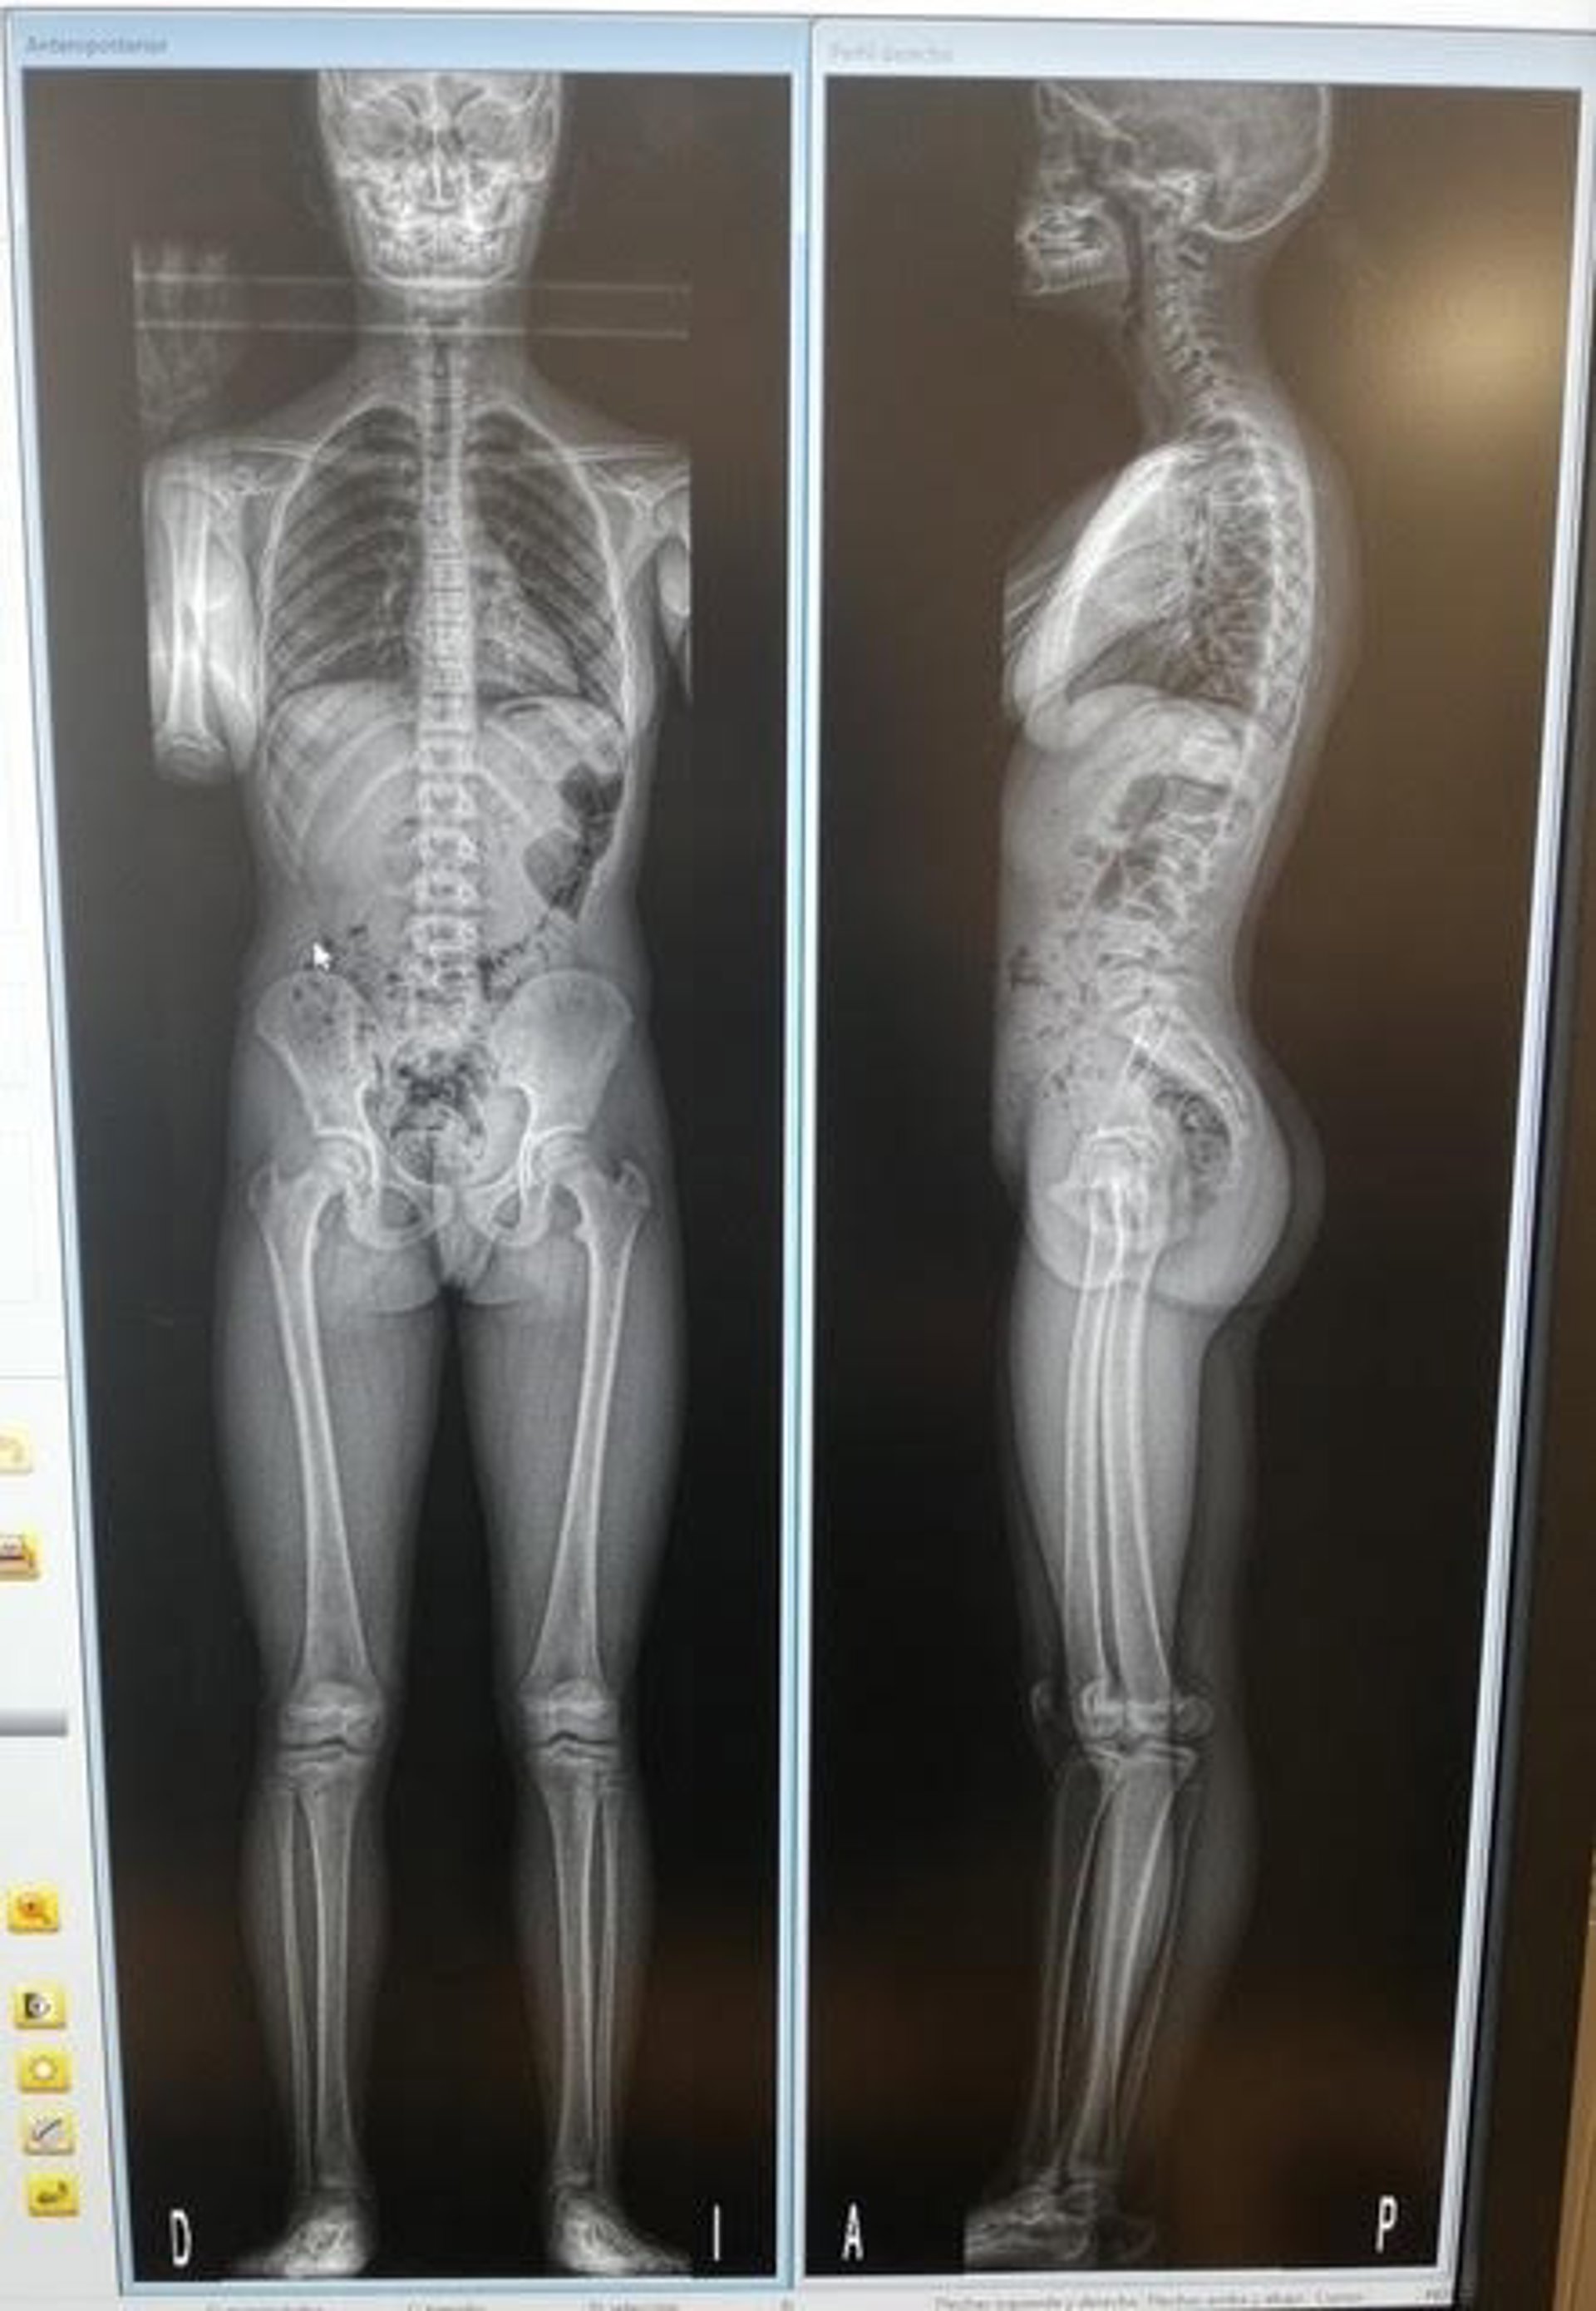

Escáner EOS Edge .

Escáner EOS Edge . - INSTITUTO CLAVEL

Además, habrá jornada de puertas abiertas para conocer el escáner EOS Edge una instalación radiológica de alta resolución que permite hacer dos barridos desde la cabeza a los pies, de perfil y de frente. El resultado es mucho más preciso que el de una radiografía convencional y con menos radiación, señalan los especialistas.